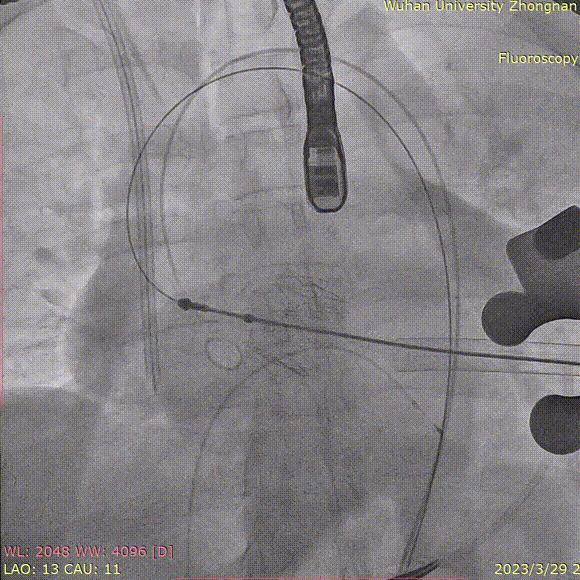

释放瓣膜,复查根部造影,未见明显反流,瓣膜形态和位置满意,双侧冠脉未见遮挡征象:

退出介入器:

血管减影造影,瓣膜形态正常、未见瓣周漏:

即刻复查食道超声,长轴切面显示瓣架深度合适,瓣叶启闭正常,未见明显瓣周漏:

彻底止血,闭合心尖手术切口,手术圆满结束。